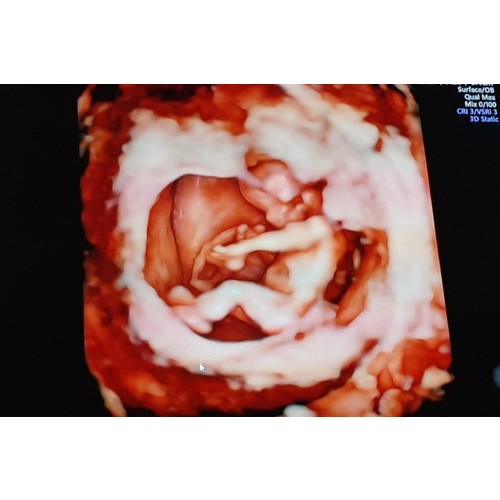

Ik heb er twee gehad in dezelfde week. Eentje was een 3d echo en eentje een 2d bij de gynaecoloog. Ik vond dit buiten beetje oncomfortabel na een tijdje geen probleem. Vooral met de 3d echo lag ik er echt een halfuur. De echo's waren gemaakt met 8 weken.

Ik ben nu 10 weken en een beetje, volgende week weer een 2d echo. Week erop weer een 3d echo.